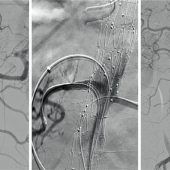

Wenn die Aorta reißt: Wie Elmar R. das Leben gerettet wurde Wasserburg – 25 Jahre lang wusste Elmar R. (67), dass er ein Aneurysma im Bauchraum hat. Ein Zufallsbefund bei einem CT wegen Rückenbeschwerden. Jährlich ging es danach zur Kontrolle, die... zum Artikel